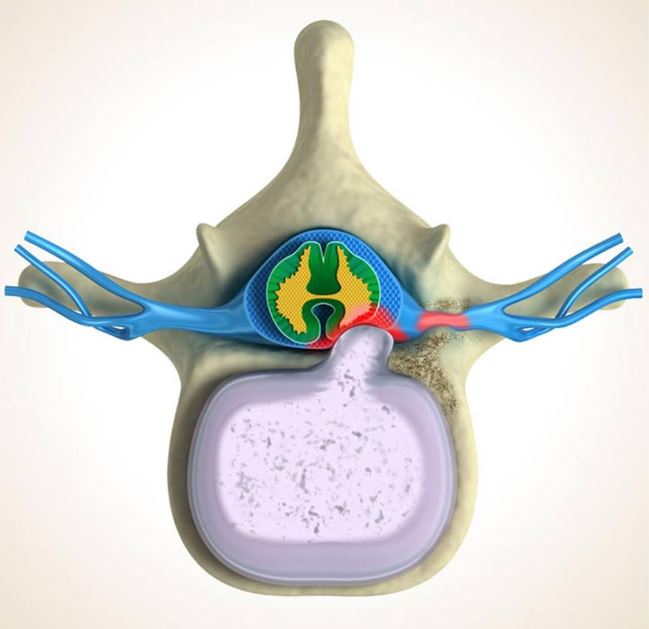

Spinal Cord Under Pressure Of Bulging Disc Stock Illustration …